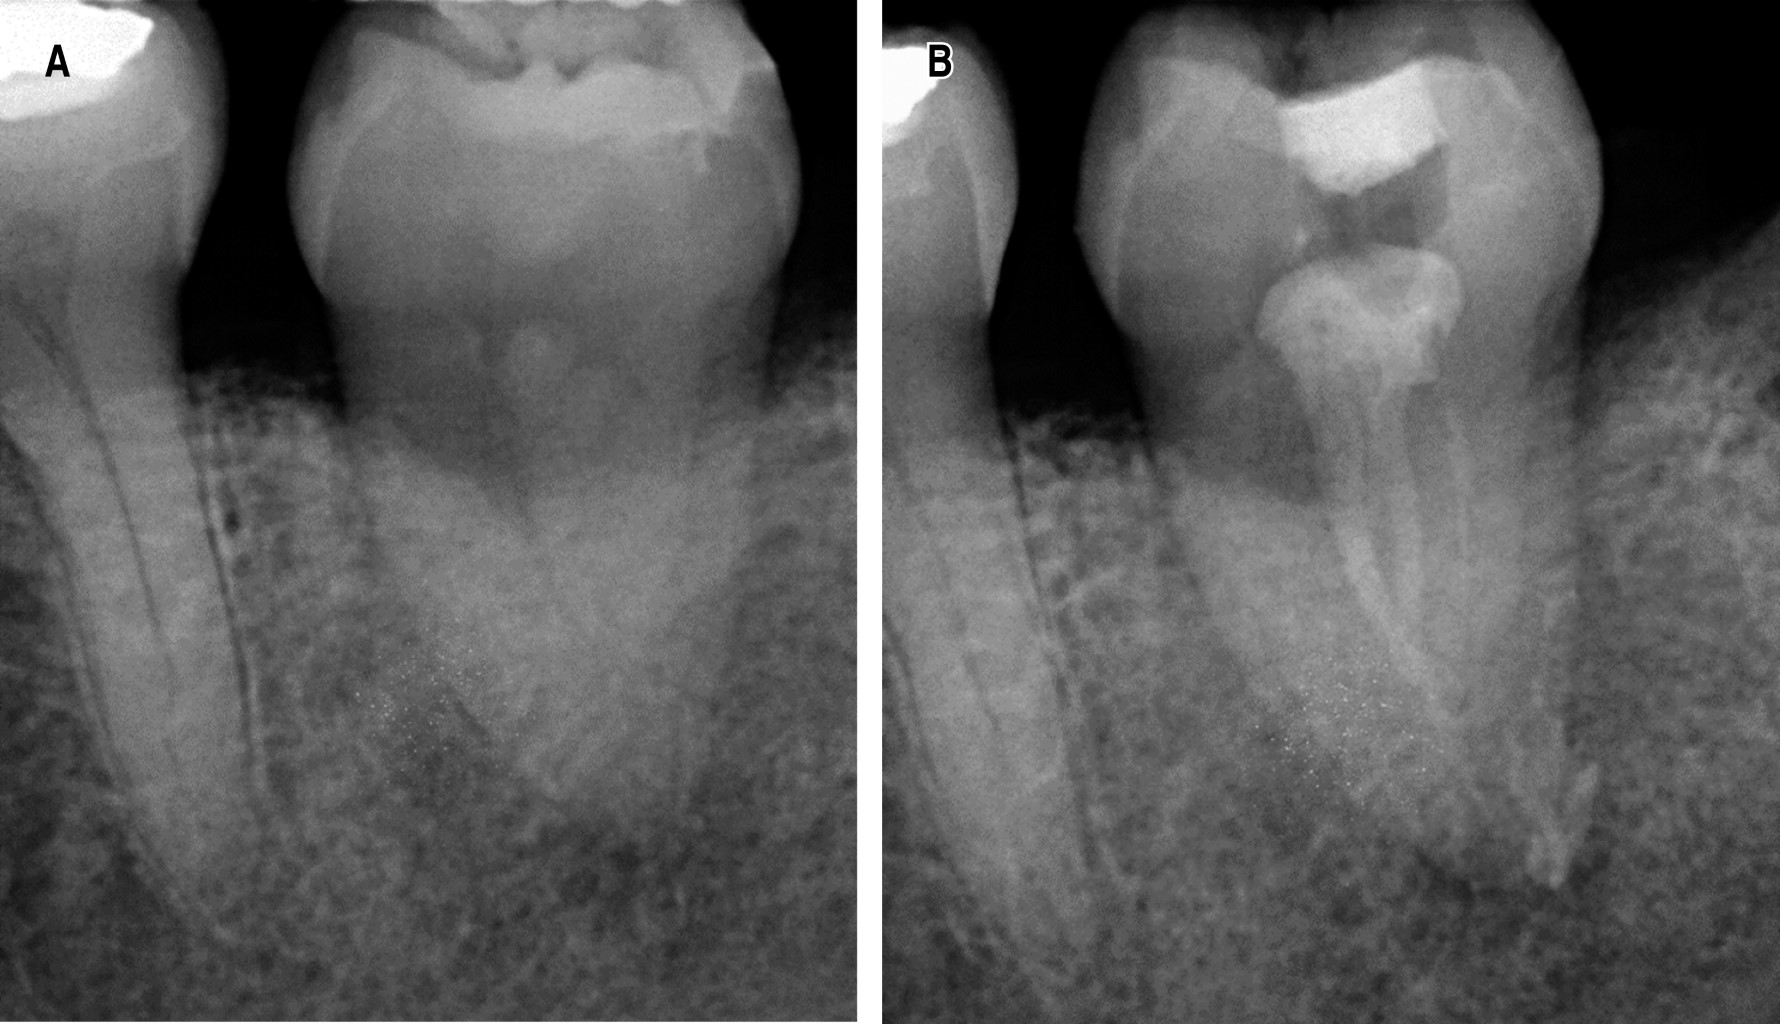

Posterior a la segunda semana del autotrasplante se realizó un primer control postoperatorio (Figura 6A). El paciente acudió con el especialista en endodoncia para realización del tratamiento de conducto con la colocación de hidróxido de calcio el cual se mantuvo en los conductos radiculares hasta el primer mes de postoperatorio, realizando así el control radiográfico (Figura 6B).

Posterior a la colocación del hidróxido de calcio, se realizó la obturación definitiva del diente autotrasplantado con gutapercha y su posterior control a los tres meses (Figura 7A), hasta su control de los seis meses (Figura 7B).